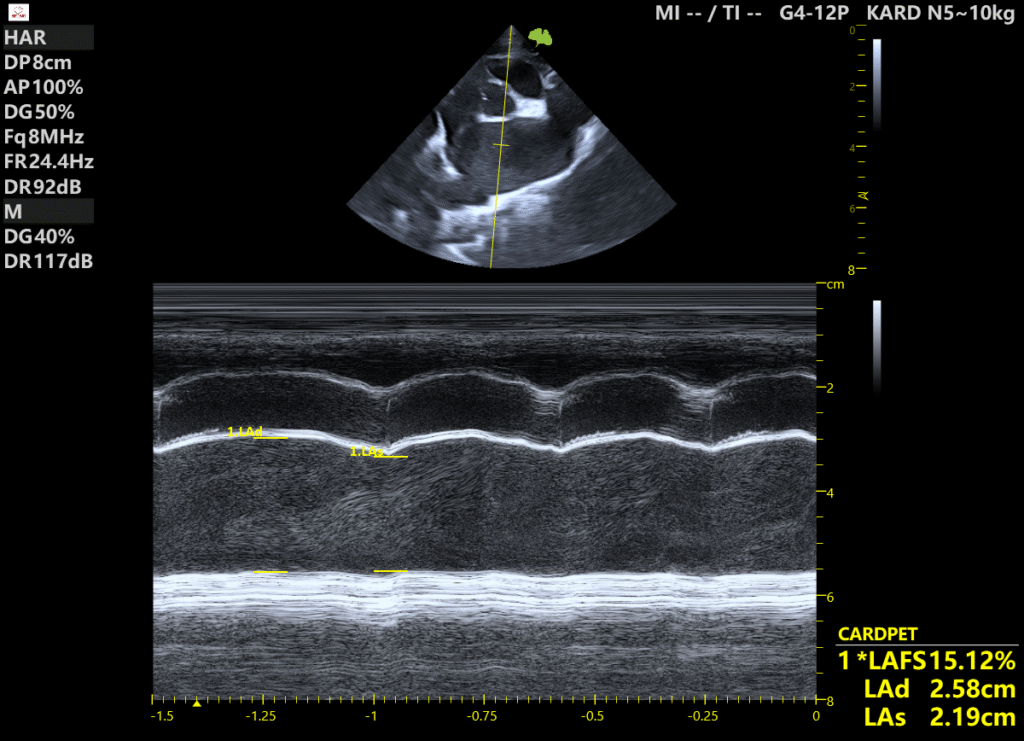

Przedstawiony pacjent to 14-letni kot, mieszaniec, u którego rozpoznano fenotypową kardiomiopatię restrykcyjną.

Pierwsze badanie echokardiograficzne: powiększony lewy przedsionek, znacznie osłabiona kurczliwość lewego przedsionka (pomiar LAFS – frakcja skracania lewego przedsionka) oraz masywny spontaniczny echokontrast (SEC).

Drugie badanie – po trzech miesiącach leczenia:

Uzyskano poprawę kurczliwości lewego przedsionka oraz zmniejszenie SEC.